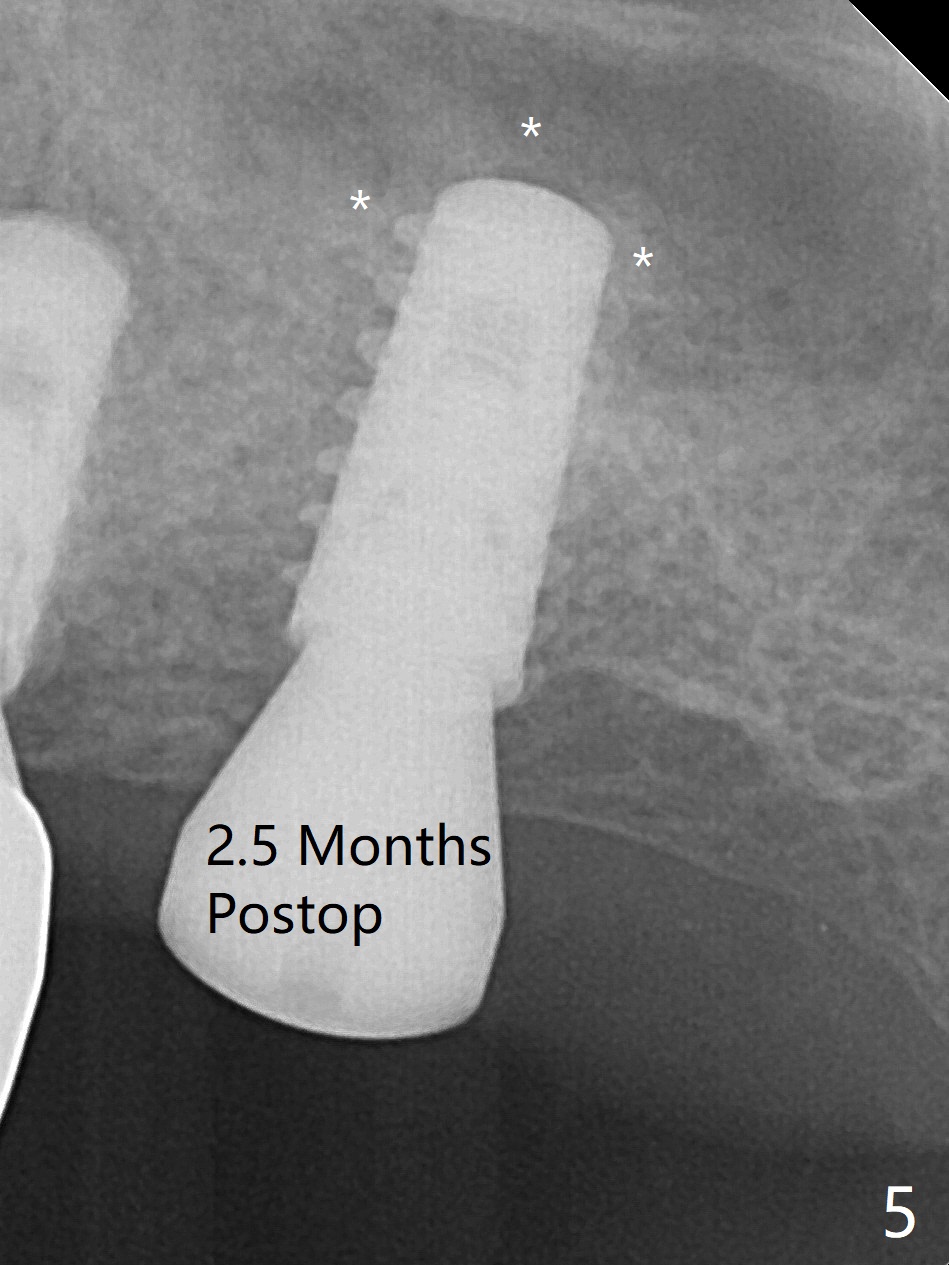

After finishing osteotomy with IS guide and Tatum Tapered tap 5x14 mm for 11 mm (gingival level) free hand, a 5x11 mm Tatum implant is placed at #18 with >15 Ncm (Fig.1). Bone harvested from the site of #18 will be used for #15 sinus lift (Fig.2 * as well as allograft). By the similar fashion, osteotomy at #15 is finished according to IS drill sequence except underdrilling (4.0x7.3 mm drill with 2 O-rings). Following use of DIO Sinus Approach Kit and placement of 2 pieces of PRF membrane and mixture of autogenous and allograft for sinus lift, a 4.5x11 mm IBS dummy implant is placed (Fig.2). With more allograft for sinus lift, a 5x9 mm implant is inserted with >35 Ncm (Fig.3). At #18 the implant 2.5 months postop (Fig.4) seems ok with removal of the cover screw and placement of a healing cuff. The implant at #15 appears osteointegrated with sinus lift 2.5 months postop (Fig.5 *). Half month later, the implant at #18 is tender associated with unipost placement. The healing abutment returns. A pair abutment (5.5x4(4) mm; 25 Ncm) is placed at #15. When the patient returns 7 months postop, BWs are taken to confirm that the abutment at #15 is fully seated, whereas that at #14 is not (Fig.6). A healing abutment is then placed at #14. Osteointegration seems to occur at #18; there is no tenderness when a 4.5x3 mm abutment is placed (Fig.7). Provisional crowns are fabricated at #15 and 18 for progressive loading. When the patient returns 14 months postop, a 5x4(4) mm hex abutment is placed at #14 with apparent gap between the implant and abutment (Fig.8 (PA) open arrow). In fact the gap seems to be absent more coronally as shown by bitewings (Fig.9,10 <). All of the 3 crowns are cemented in situ (Fig.11, 12) although the one at #14 is removed with the abutment for removal of residual cement. When the latter is re-torqued, the abutment remains completely seated (Fig.12). However, the implants at #15 and 18 appear to be placed distally with free-end guides (black lines).